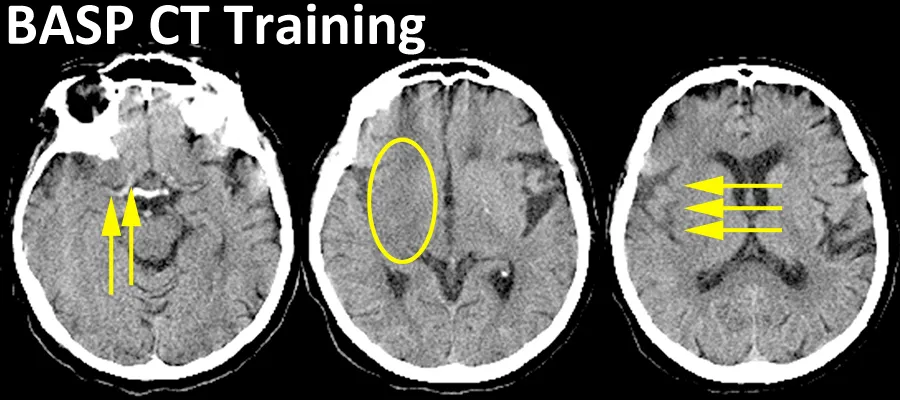

The BASP CT Training lecture teaches about how to read acute stroke CT scans. It is useful to review in advance of participation in the Acute Cerebral CT Evaluation of Stroke Study (ACCESS). Image REGISTER FOR BASP CT Training We will send you a password with which to login LOGIN TO BASP CT Training The BASP CT Training lecture was originally launched on 18 Dec 2003 The BASP CT Training lecture was re-launched on 21 Nov 2018 There are about 180 slides so expect to spend about 90 minutes / 1.5 hours working through the materials Quick links Participate in & train using BASP CT Training slides here Follow on & test yourself against experts, with the ACCESS series of 63 acute stroke CT scans Integrate imaging training with STARS Thrombolysis Masterclass Background The BASP CT Training lecture was developed in 2003. Its aim is to help those who need to review CT brain scans for bleeding & infarct signs, in the context of a patient with stroke symptoms, for example: Stroke Physicians Emergency / Acute Medicine doctors Geriatricians Radiology trainees / registrars / residents It was developed by the University of Edinburgh Imaging group in conjunction with the British Association of Stroke Physicians (BASP). Participation Participate in & train using BASP CT Training slides here Follow on & test yourself against experts, with the ACCESS series of 63 acute stroke CT scans Feedback from participants indicates that the BASP CT Training lecture is useful before embarking on the Acute Cerebral CT Evaluation of Stroke Study (ACCESS). It has been used for training: Third International Stroke Trial (IST-3) centres British Association of Stroke Physicians (BASP) doctors in training Completing the BASP CT Training lecture may be helpful if: You are introducing a new thrombolysis service You are likely to be working in a unit where you will see many acute stroke patients You feel that your scan reading skills are either rusty or have never been developed in the first place Relevant links Register for BASP CT Training here Login to BASP CT Training here ACCESS - the Acute Cerebral CT Evaluation in Stroke Study ECCITING - Edinburgh Criteria for CAA-associated ICH Training Please link to the short url for the British Association of Stroke Physicians (BASP) CT training lecture webpage: www.ed.ac.uk/edinburgh-imaging/basp-ct-training This article was published on 2024-08-22